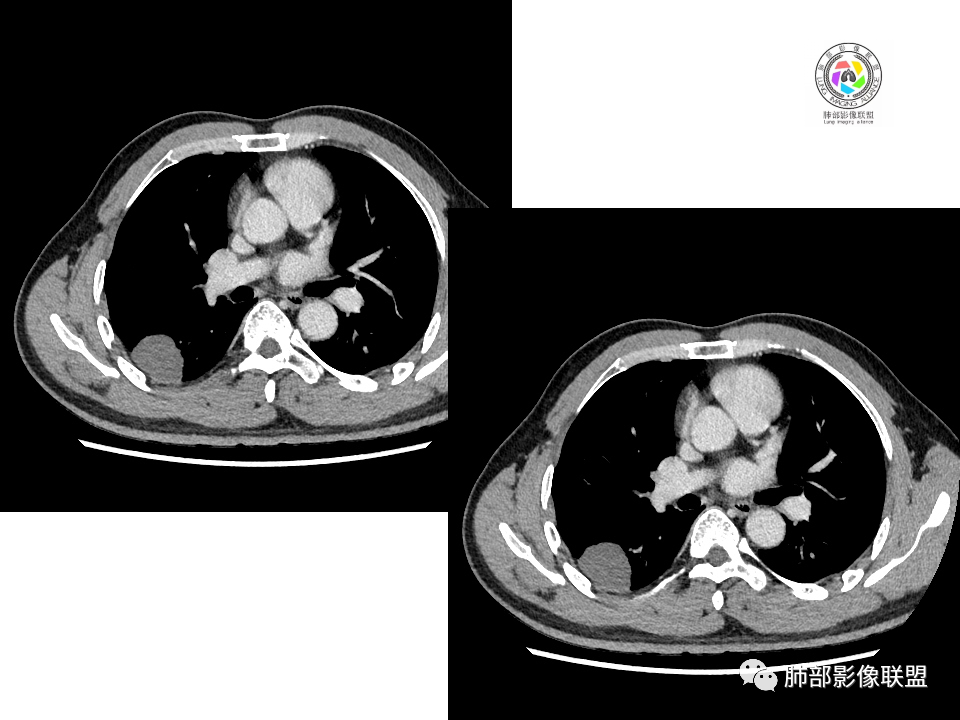

2.右肺下叶背段胸膜下块影,边界清楚光整,上下极见磨玻璃晕,未见明显分叶毛刺和棘状突起,未见胸膜凹陷或胸壁侵入。密度均匀,轻度不均匀强化。未见支气管进入。

1.边缘光整干净,大病灶缺乏坏死等,不符合鳞癌影像学特征。尽管有吸烟史,还是偏年轻。

2.边缘光整,会是小细胞癌或是大细胞癌吗?小细胞癌的肺门纵隔淋巴结增大往往十分夸张,该患者不符合。

注意,基底段支气管血管束旁的小结节影,即便是淋巴结,也与背段病灶引流途径不符。

3.会是转移瘤吗?如前所述,患者偏年轻,缺乏相关原发肿瘤病史,强化程度不高,似乎也缺乏支持点。

4.良性占位绕不过去,如发生于该部位的孤立性纤维瘤等……

有老师分析,多发病灶有磨玻璃晕,可以符合隐球菌感染,确实如此。但背段边缘如此锐利的块影还是更容易让人联想到新生物。